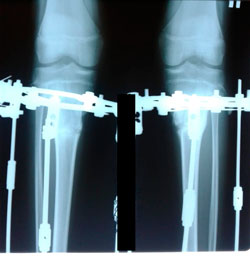

Исходник - 13 лет.

Диагноз: варусная деформация голеней + Ротация с обеих сторон.

Дата операции - 30.06.2020